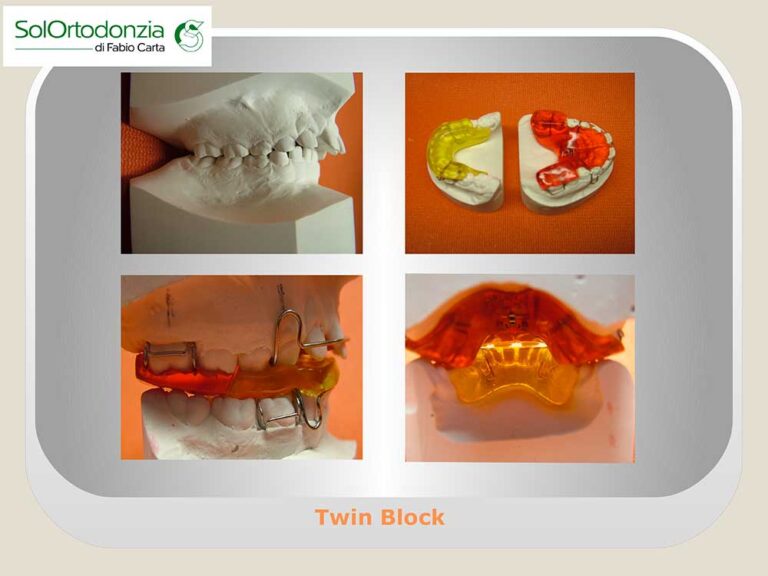

- Ortodonzia funzionale